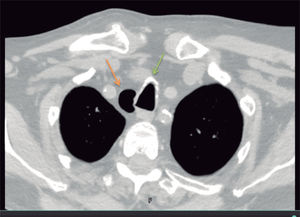

Traqueocele: hallazgo incidental muy infrecuente